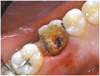

Le morceau fracturé a été enlevé. La fracture est en biseau et va loin sous la gencive.